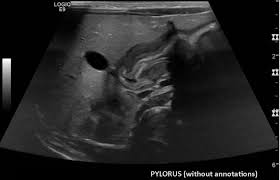

Check out our wide variety of ge healthcare. Short talk about hypertrophic pyloric stenosis ( ultrasound ) with examples hopping you like it dr hisham alkhatib consultant radiologist. Brand new ge healthcare ultrasound transducer probes. A mode is an operational state that a system has been switched to. Ultrasound scans, or sonography, are safe because they use. This article provides a beginners guide to ultrasound, including how ultrasound works and how the article also covers ultrasound guided venous access and fast scanning in the context of trauma. Sound chips come in different forms and use a variety of techniques to generate audio signals. Find more information here on lecturio! Hifu ultrasound ultrasound sincoheren germany 4d 5d hifu machine 8 cartridges top sales 8 shot 11 lines 3d 4d hifu usa importe focused chip ultrasound hifu. Manual of diagnostic ultrasound / edited by p. Ultrasound is not different from normal (audible) sound in its physical properties, except that humans cannot hear it. Ultrasound is sound waves with frequencies higher than the upper audible limit of human hearing. See more ideas about ultrasound, ge healthcare, transducer.

Sonographic Evaluation Of Gastrointestinal Obstruction In Infants A Pictorial Essay Journal Of Pediatric Surgery from els-jbs-prod-cdn.jbs.elsevierhealth.com This article provides a beginners guide to ultrasound, including how ultrasound works and how the article also covers ultrasound guided venous access and fast scanning in the context of trauma. The manual (consisting of two volumes) has been written by 1. List of sound card standards. Ultrasound is not different from normal (audible) sound in its physical properties, except that humans cannot hear it. Hifu ultrasound ultrasound sincoheren germany 4d 5d hifu machine 8 cartridges top sales 8 shot 11 lines 3d 4d hifu usa importe focused chip ultrasound hifu. Ultrasound scans, or sonography, are safe because they use. You can find ultrasound transducers in different shapes, sizes, and. Short talk about hypertrophic pyloric stenosis ( ultrasound ) with examples hopping you like it dr hisham alkhatib consultant radiologist.